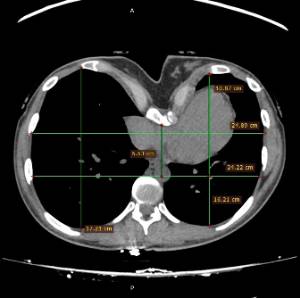

Los datos médicos del paciente, más la exploración clínica realizada por el equipo de cirugía, junto a un análisis pormenorizado de las imágenes del TAC y las reconstrucciones digitales en 3D de cada tórax realizadas conjuntamente con el equipo de ingenieros de Ventura Medical Technologies, son la base para determinar si la técnica Pectus Up está indicada y como se debe proceder en cada uno de los pacientes.

Con estos datos se selecciona el implante que mejor se ajustar a la anatomía de cada tórax, la ubicación exacta del sistema de elevación y, a su vez, proporciona al equipo quirúrgico un detalle de los pasos a tener en cuenta para llevar a cabo una correcta implantación.

| Pectus Excavatum | Pectus Excavatum Asimétrico |

|---|---|

| Índice de Asimetría | 0.6 (+R/-L)(|AI|> 0.05 Asimétrico) |

| Índice de Haller | 4.5 (HI >3.5) |

| Índice de Corrección | 49.13% |

| Rotación esternal | 18.1 ° (a la derecha) |

Informe de evaluación del TAC de un paciente enviada al cirujano